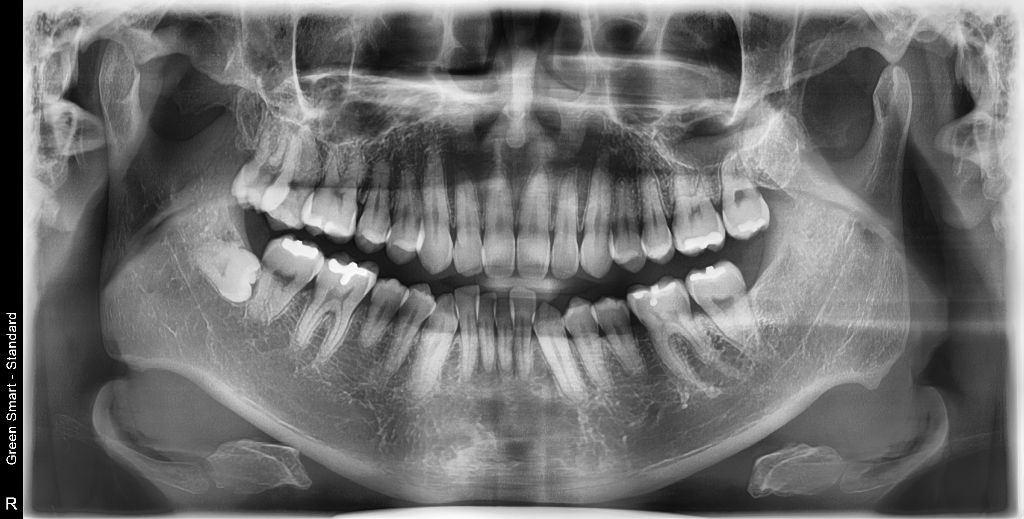

현재 저는 상악 7번 대구치 가위교합( 바깥쪽) 나와 있는 상황입니다. 7번,8번 모두 치아 상태는 괜찮다고 들었습니다.

A선생님은 7번 옮기다가 뿌리 상할 수 도 있고, 8번 상태 좋으니 7번 발치 후 8번 대체 권유하시고

다른 선생님은 8번은 크기도 약간 작고, 추후 신경치료 등 장기적인 관점에서 8번 발치 7번 사용을 권유 하셨습니다...

• 1번 째 사진